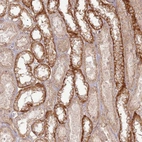

Immunohistochemical staining of human kidney shows distinct cytoplasmic positivity in distal tubules.